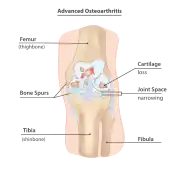

Osteoarthritis is another disease that has a strong association with bone marrow edema due to mechanical loading, as well as stress on the subchondral region.[33][34]

Diagnosis of trabecular edema is primarily done via magnetic resonance imaging (MRI). The presence of edema within the bone marrow yields a visible signal on the MRI, due to displacement of the normally fatty tissue within the marrow by interstitial fluid with higher water content; this change in composition is then reflected by the MRI due to differences in the T1-weighted and T2-weighted images.[5][1]

A healthy bone is rich in fat and has lower water content, therefore it appears as bright signals on T1-weighted images and dark on T2-weighted images.[2] Conversely, regions with trabecular edema has lower fat and higher water content. Hence, they have a comparatively lower intensity than normal bone tissues on a T1-weighted image, and a higher intensity on a T2-weighted image.[42]